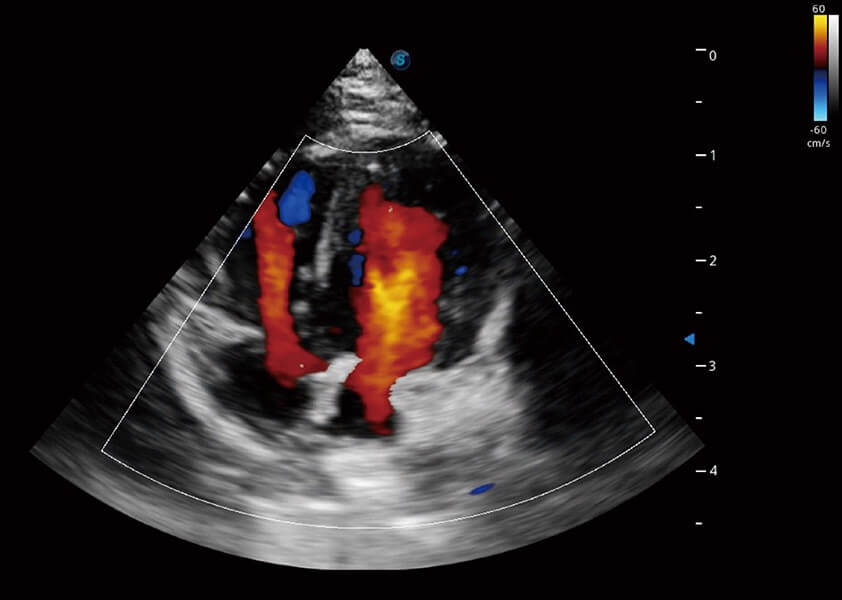

(犬)四腔心血流